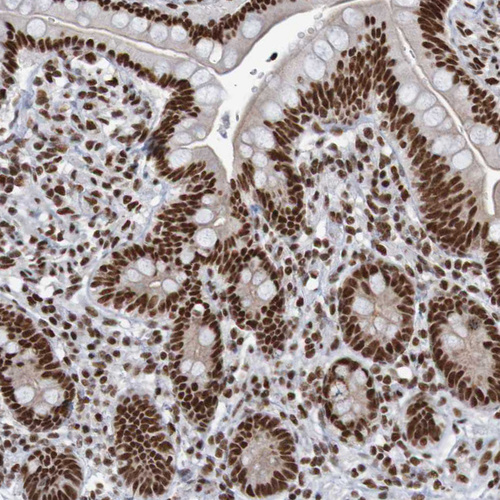

Immunohistochemical staining of human prostate shows strong nuclear positivity in glandular cells.